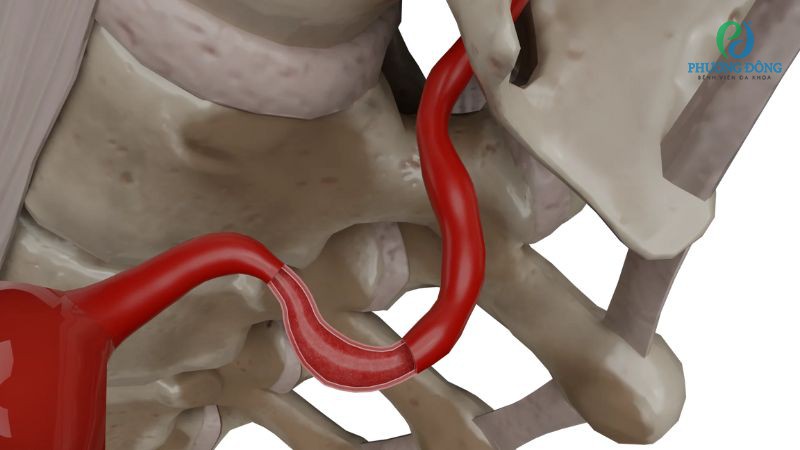

- V3 (đoạn ngoài màng cứng) uốn cong quanh phần trên đốt sống C1 rồi đi vào hộp sọ.

- Hội chứng cung thủ tương đối hiếm gặp, xảy ra khi một phần xương phát triển bất thường chèn ép lên động mạch đốt sống và làm giảm lưu lượng máu lên não.